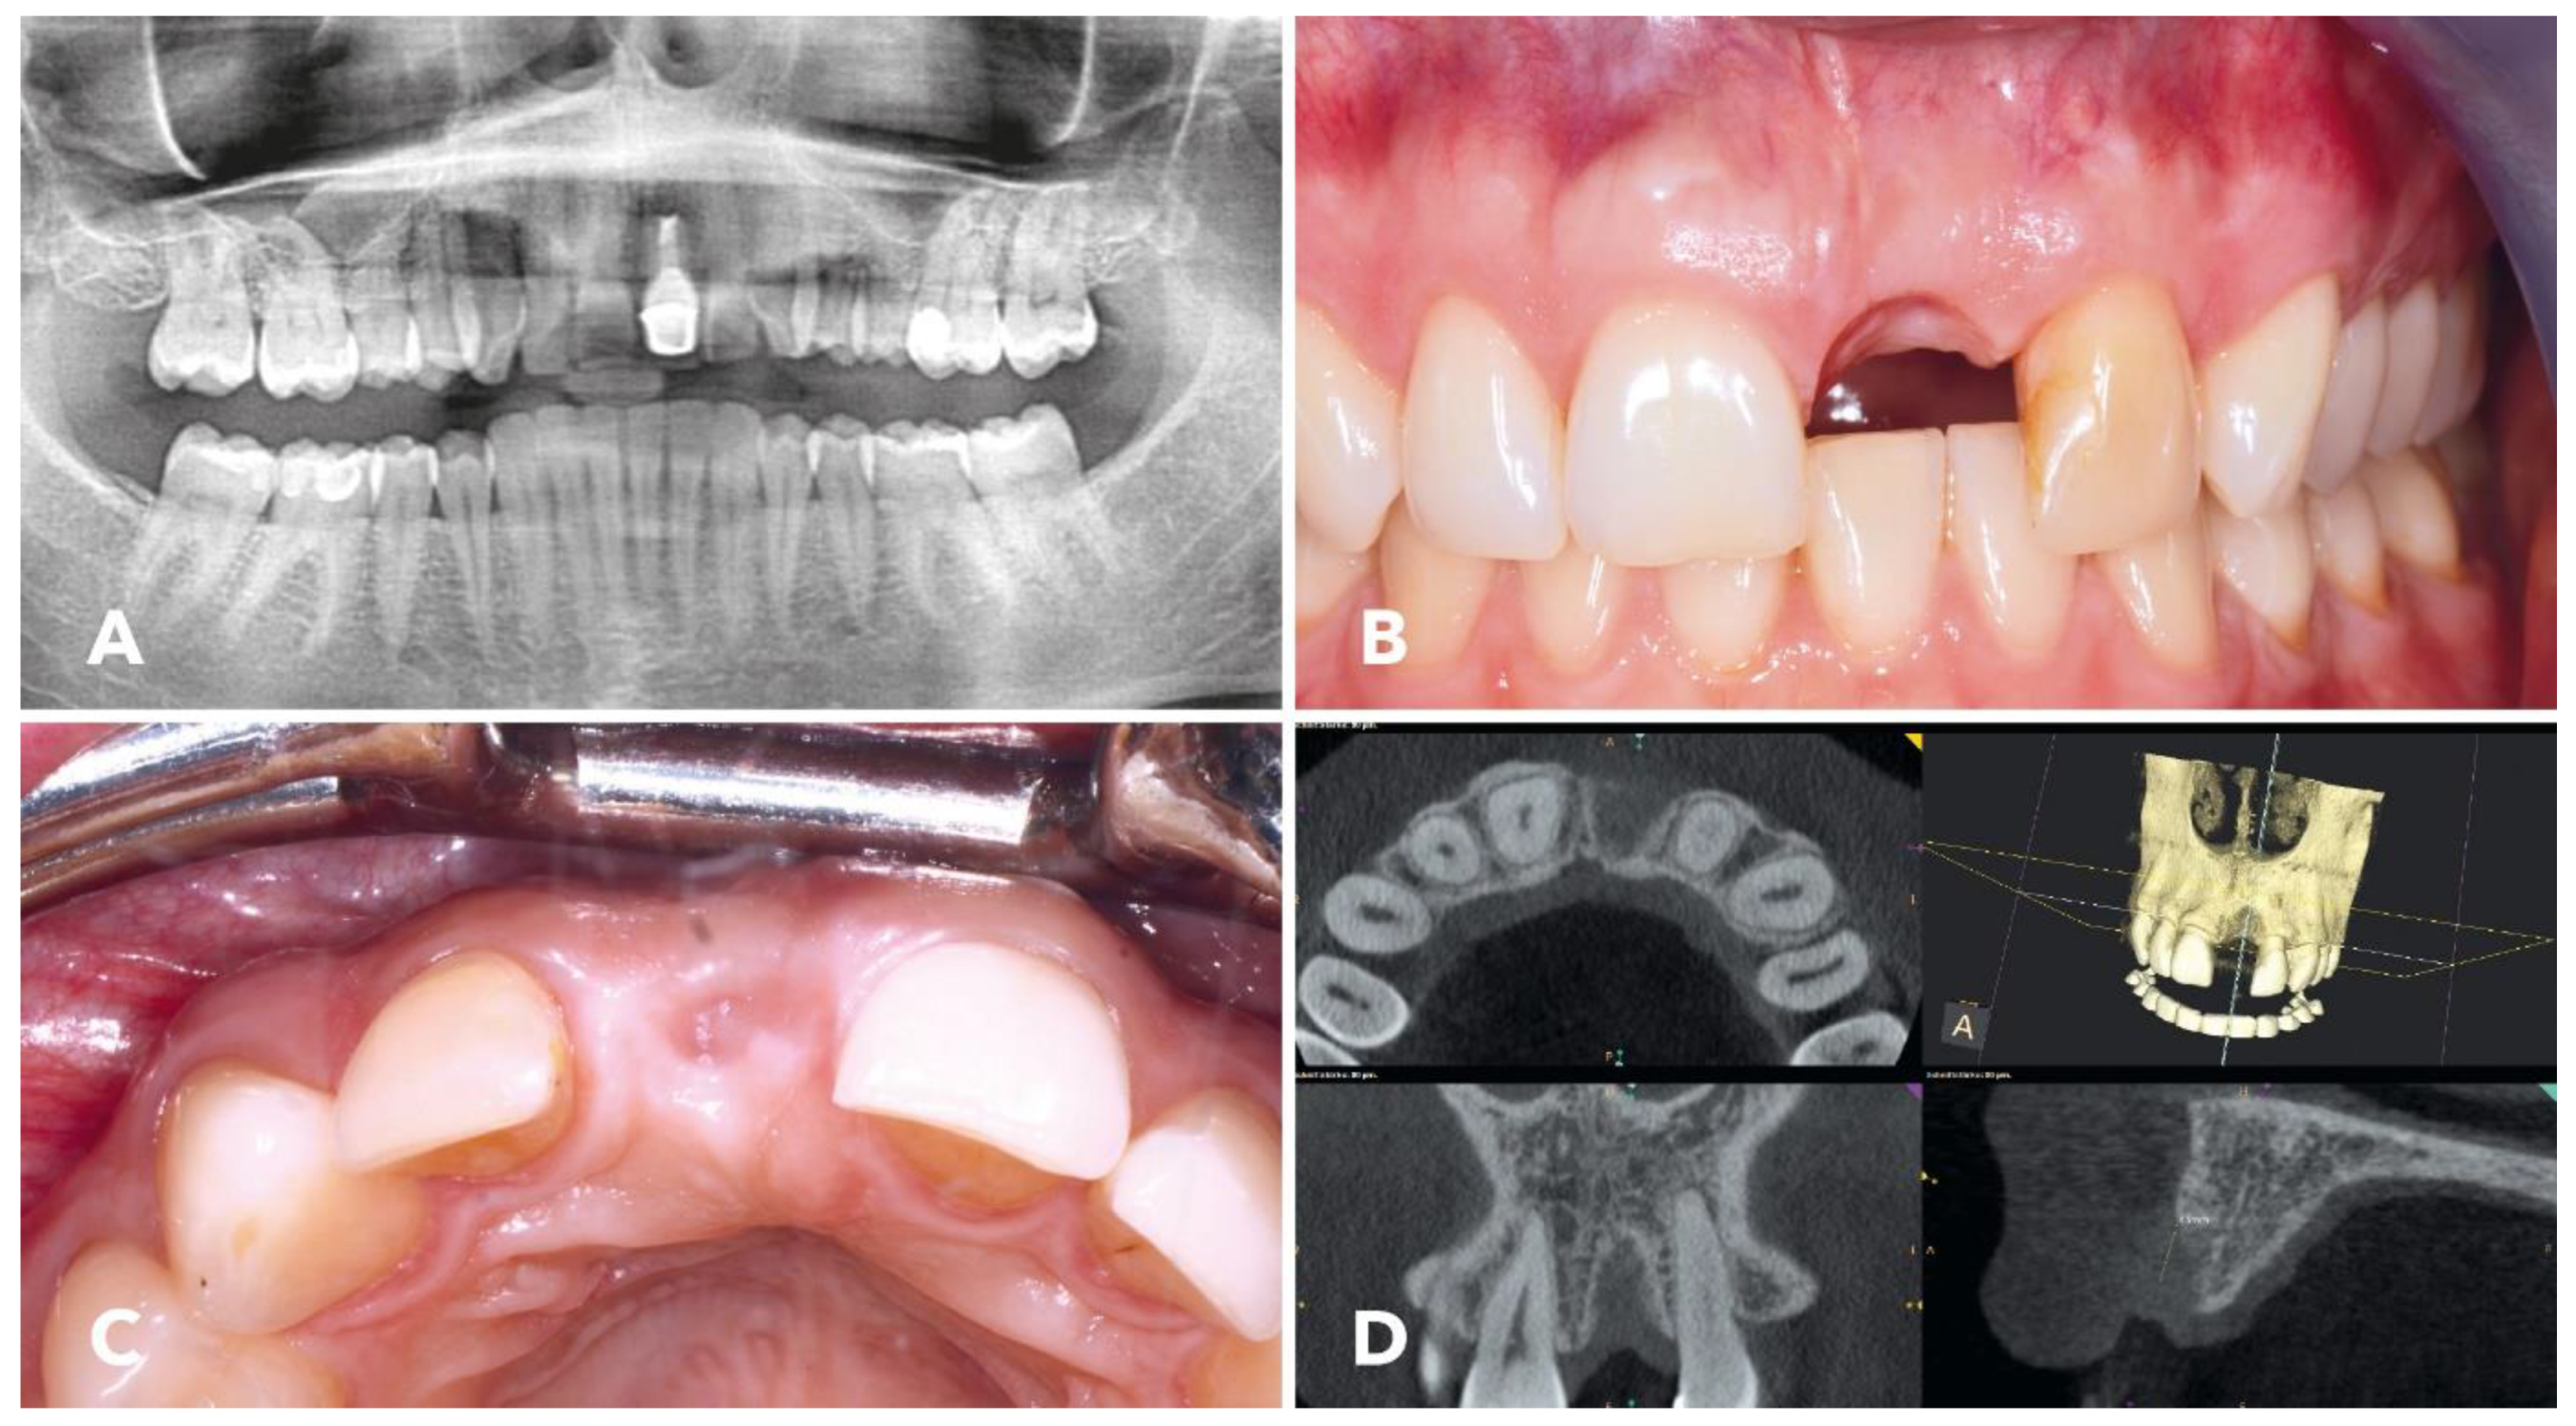

2.1. Overview of the Clinical Case

2.4. Surgical Procedure